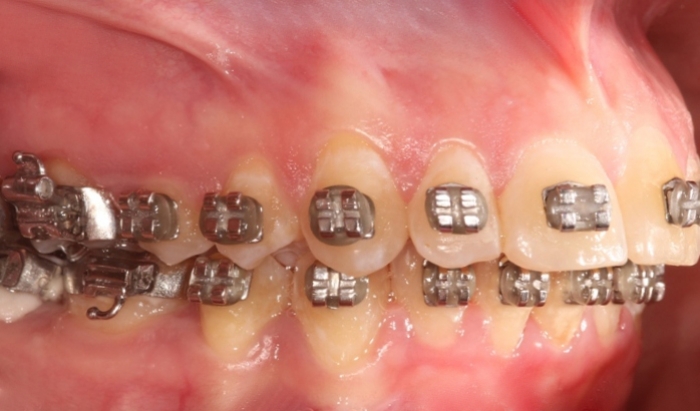

Mordida após a cirurgia